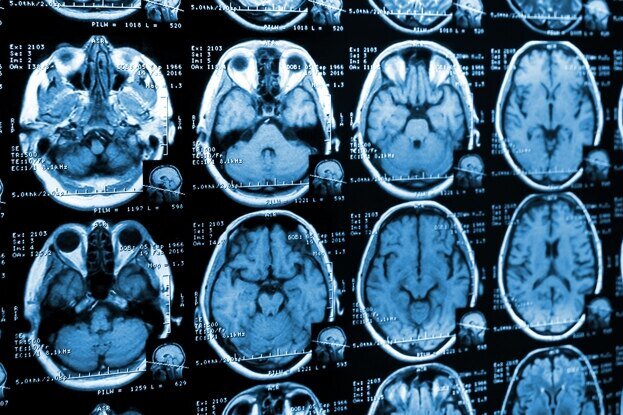

Ученые выяснили, как пристрастие к кокаину убивает мозг человека

С возрастом наш мозг претерпевает множество изменений, вплоть до того, как транслируется его ДНК. Новое исследование показало, что у людей с расстройством, связанным с употреблением кокаина, эти изменения могут накапливаться с ускоренной скоростью.

Считается, что расположенная в префронтальной коре — передней части мозга, расположенной за лбом, — зона Бродмана 9 (BA9) важна для самосознания и тормозного контроля; двух факторов, которые замешаны в расстройствах, связанных с употреблением психоактивных веществ.